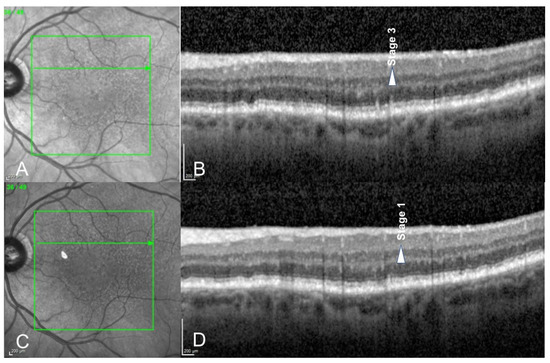

- Querques, G.; Canoui-Poitrine, F.; Coscas, F.; Massamba, N.; Querques, L.; Mimoun, G.; Bandello, F.; Souied, E.H. Analysis of Progression of Reticular Pseudodrusen by Spectral Domain–Optical Coherence Tomography. Investig. Ophthalmol. Vis. Sci. 2012, 53, 1264–1270. [Google Scholar] [CrossRef] [PubMed]